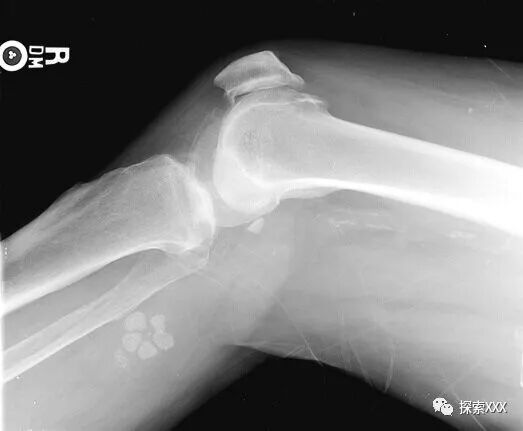

34年后的2013年10月22日,58岁的特里的腿完全瘫痪了。他被送到德克萨斯州达拉斯退伍军人管理局医疗中心放射科。一名放射科医生告诉特里,他右膝上方有一个异常物体,是金属制成的,上面连着电线。

特里·洛夫莱斯腿中的花瓣状异物

医生想知道发生了什么事,想知道这个金属物体是如何进入特里的右腿的。但特里表示他什么也不知道。放射科医生说,肯定有疤痕组织,并检查了特里的皮肤表面和嵌入金属植入物的皮下组织的X射线照片。经过详细检查后,医生承认他找不到任何疤痕组织。

此外,在特里右膝的X光检查中,还有一个花瓣状物体发出白光。医生推测这是贝克囊肿,是一种充满液体的囊肿,会导致膝盖后面隆起和紧绷感。但医生承认他以前从未见过具有如此均匀的几何形状的贝克囊肿。同时,医生表示,根据这些异物的密度,他认为它们与骨头的密度相同。因此,他们认为这更像是一种植入物。